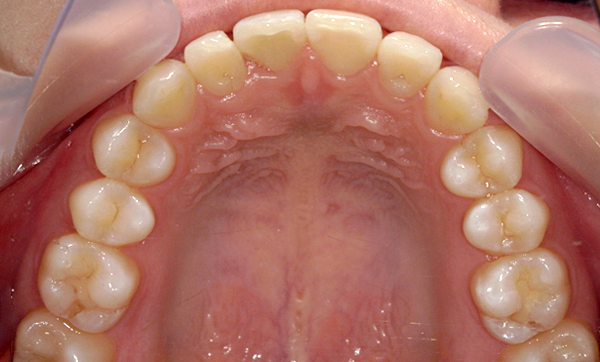

症例_009 「上下の前歯」症例

治療期間:7ヶ月金額:54万円+税20代女性捻転歯一部の反対咬合前歯のガタガタ

Before | After |